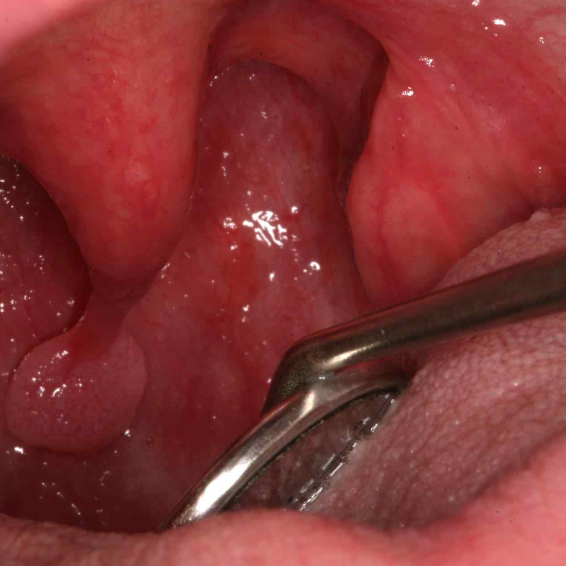

이렇게 붓고 편도 사이에 작은 구멍이 점차 커지면서 여기에 찌꺼기나 기타 이물질이 앉으면서 굳어지면 으… 상상하니 좀 무섭긴 하지만 어쨌든 그 알갱이가 편도결석!

치료 방법은 정도에 따라 다양하지만 소량으로 어디에 위치했는지 정확히 확인되면 이비인후과에서 핀셋 등으로 뽑거나 흡입기를 통해 제거하기도 합니다.

저는 육안으로 결석이 보이는 상태가 아니기 때문에 시간이 좀 걸렸지만 사용 시 중요한 고강도 압력으로 분사하면 흠집이 날 수 있기 때문에 사전에 충분히 아프지 않을 정도의 압력으로 테스트 후 사용해 주시기 바랍니다.

이물감이 느껴지는 부위 주위를 계속 시도했더니 갑자기 걸리는 느낌이 없어졌어요. 양치질을 해보니 오…드디어 나온 저를 괴롭혀온 결석